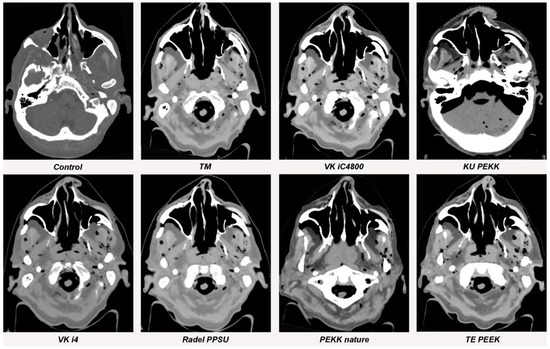

3.1. Streak Artifacts

3.1.1. Implant Material

3.1.2. Metallic Artifact Reduction Algorithm

3.2. Blooming Artifacts

3.2.1. Implant Material

3.2.2. Metallic Artifact Reduction Algorithm

3.3. Image Quality